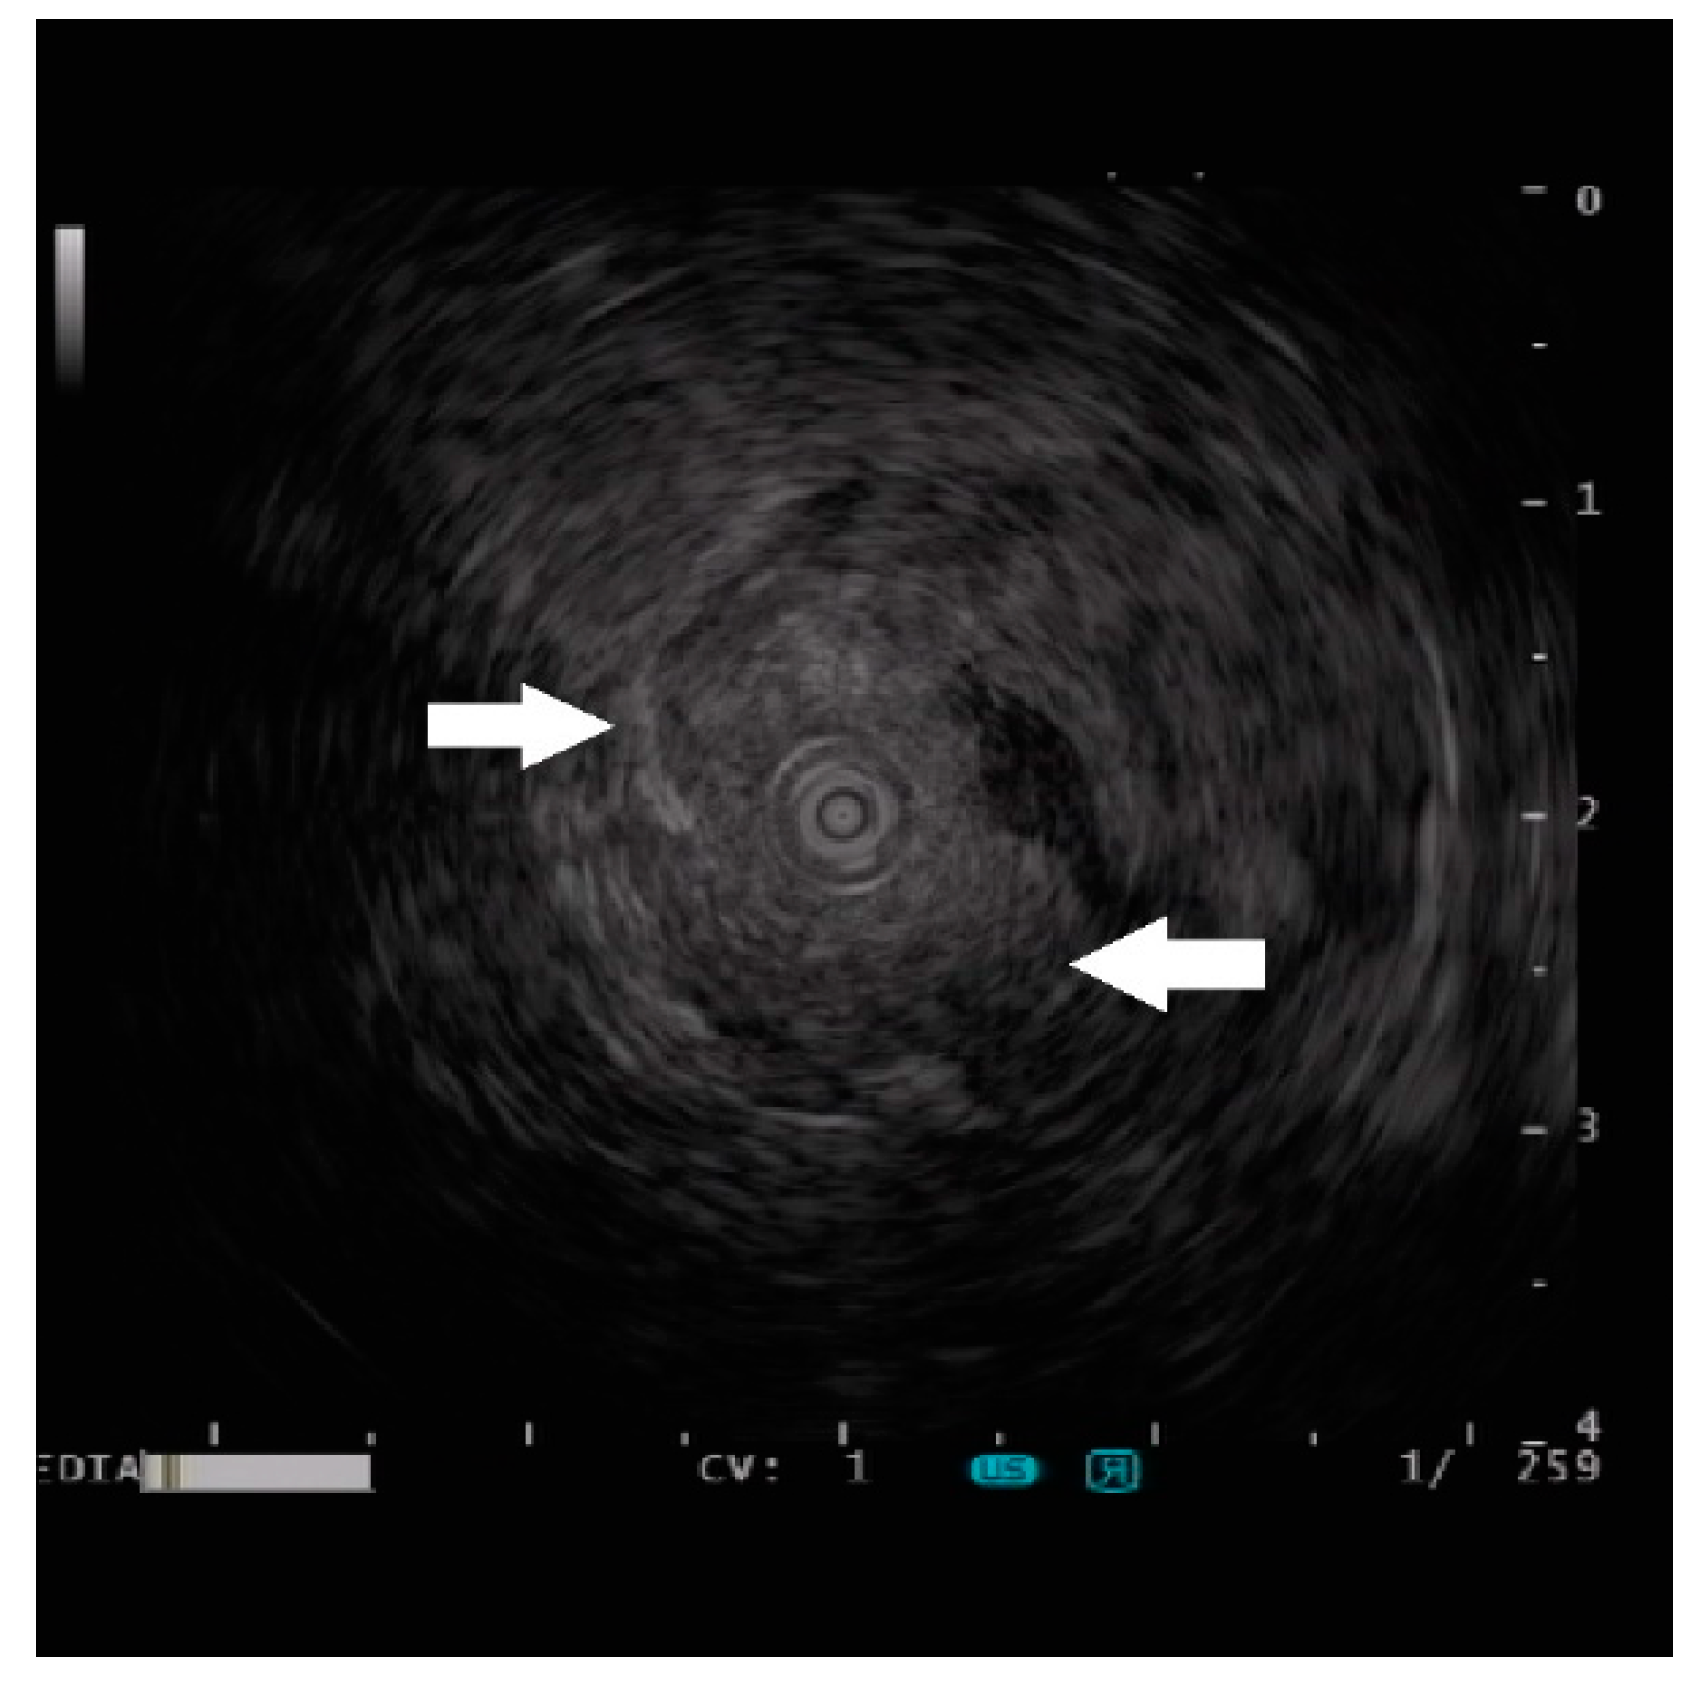

Endoscopic Ultrasound Appearance of Jejunal Ectopic Pancreas Mimicking Metastatic Nodule in a Cancer Patient

Lee, C.-W.; Lin, Y.-C.; Hsu, H.-T.; Chen, Y.-Y.; Yen, H.-H. Endoscopic Ultrasound Appearance of Jejunal Ectopic Pancreas Mimicking Metastatic Nodule in a Cancer Patient. Diagnostics 2023, 13, 660. https://doi.org/10.3390/diagnostics13040660